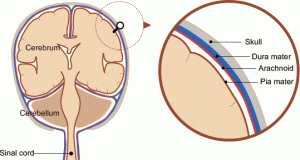

Ο εγκέφαλος καλύπτεται από τρεις διακριτές μεμβράνες, τις μήνιγγες. Η μεσαία από αυτές λέγεται αραχνοειδής μήνιγγα. Κάτω από την αραχνοειδή μήνιγγα και γύρω από τον εγκέφαλο υπάρχει ένας στενός κενός χώρος μέσα στον οποίο κυκλοφορεί εγκεφαλονωτιαίο υγρό και μέσα στον οποίο φιλοξενούνται τα μεγάλα αιμοφόρα αγγεία του εγκεφάλου (αρτηρίες και φλέβες). Αυτός ο χώρος ονομάζεται υπαραχνοειδής χώρος. Η υπαραχνοειδής αιμορραγία λέγεται, έτσι γιατί το αίμα «χύνεται» έξω από ένα μεγάλο αιμοφόρο αγγείο του εγκεφάλου (συνήθως, από μια αρτηρία) προς τον υπαραχνοειδή χώρο. Στις περισσότερες περιπτώσεις αιτία της αιμορραγίας είναι η ρήξη («σπάσιμο») ενός προϋπάρχοντος ανευρύσματος σε από τις μεγάλες αρτηρίες του εγκεφάλου.